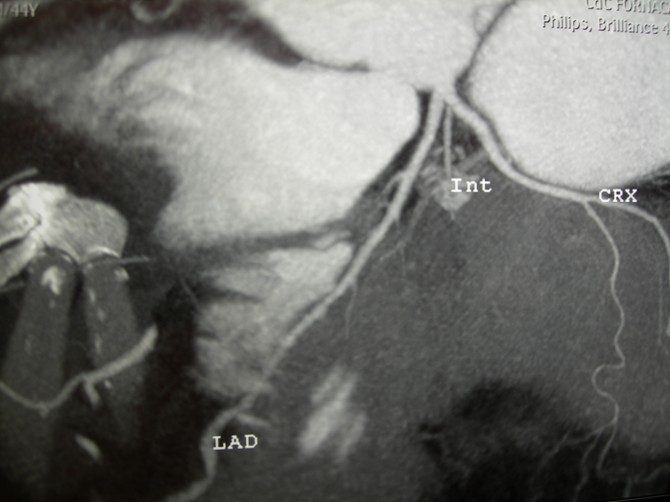

coronaro TC